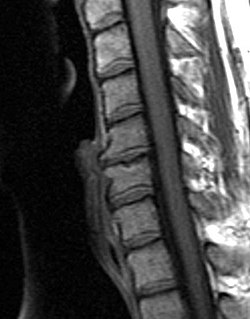

Hi there! So let's talk about degenerative disc disease. Do you know what our spine is? It's like a big tower of blocks that helps us stand up tall and move around. Each block is called a vertebrae, and in between each vertebrae, there is a soft cushion called a disc. These discs help absorb shock when we move around.

Now, sometimes as we get older, these discs can start to wear down. This is called "degeneration". It's kind of like when you play with your favorite toy a lot and it starts to get a little bit broken over time. When these discs start to degenerate, they can become less flexible and less able to absorb shock, which can cause some discomfort or pain in our backs.